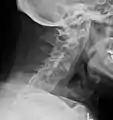

The earliest changes demonstrable by plain X-ray shows erosions and sclerosis in sacroiliac joints. Progression of the erosions leads to widening of the joint space and bony sclerosis. X-ray spine can reveal squaring of vertebrae with bony spur formation called syndesmophyte. This causes the bamboo spine appearance. A drawback of X-ray diagnosis is the signs and symptoms of AS have usually been established as long as 7–10 years prior to X-ray-evident changes occurring on a plain film X-ray, which means a delay of as long as 10 years before adequate therapies can be introduced.[24]

Lateral X-ray of the neck in ankylosing spondylitis